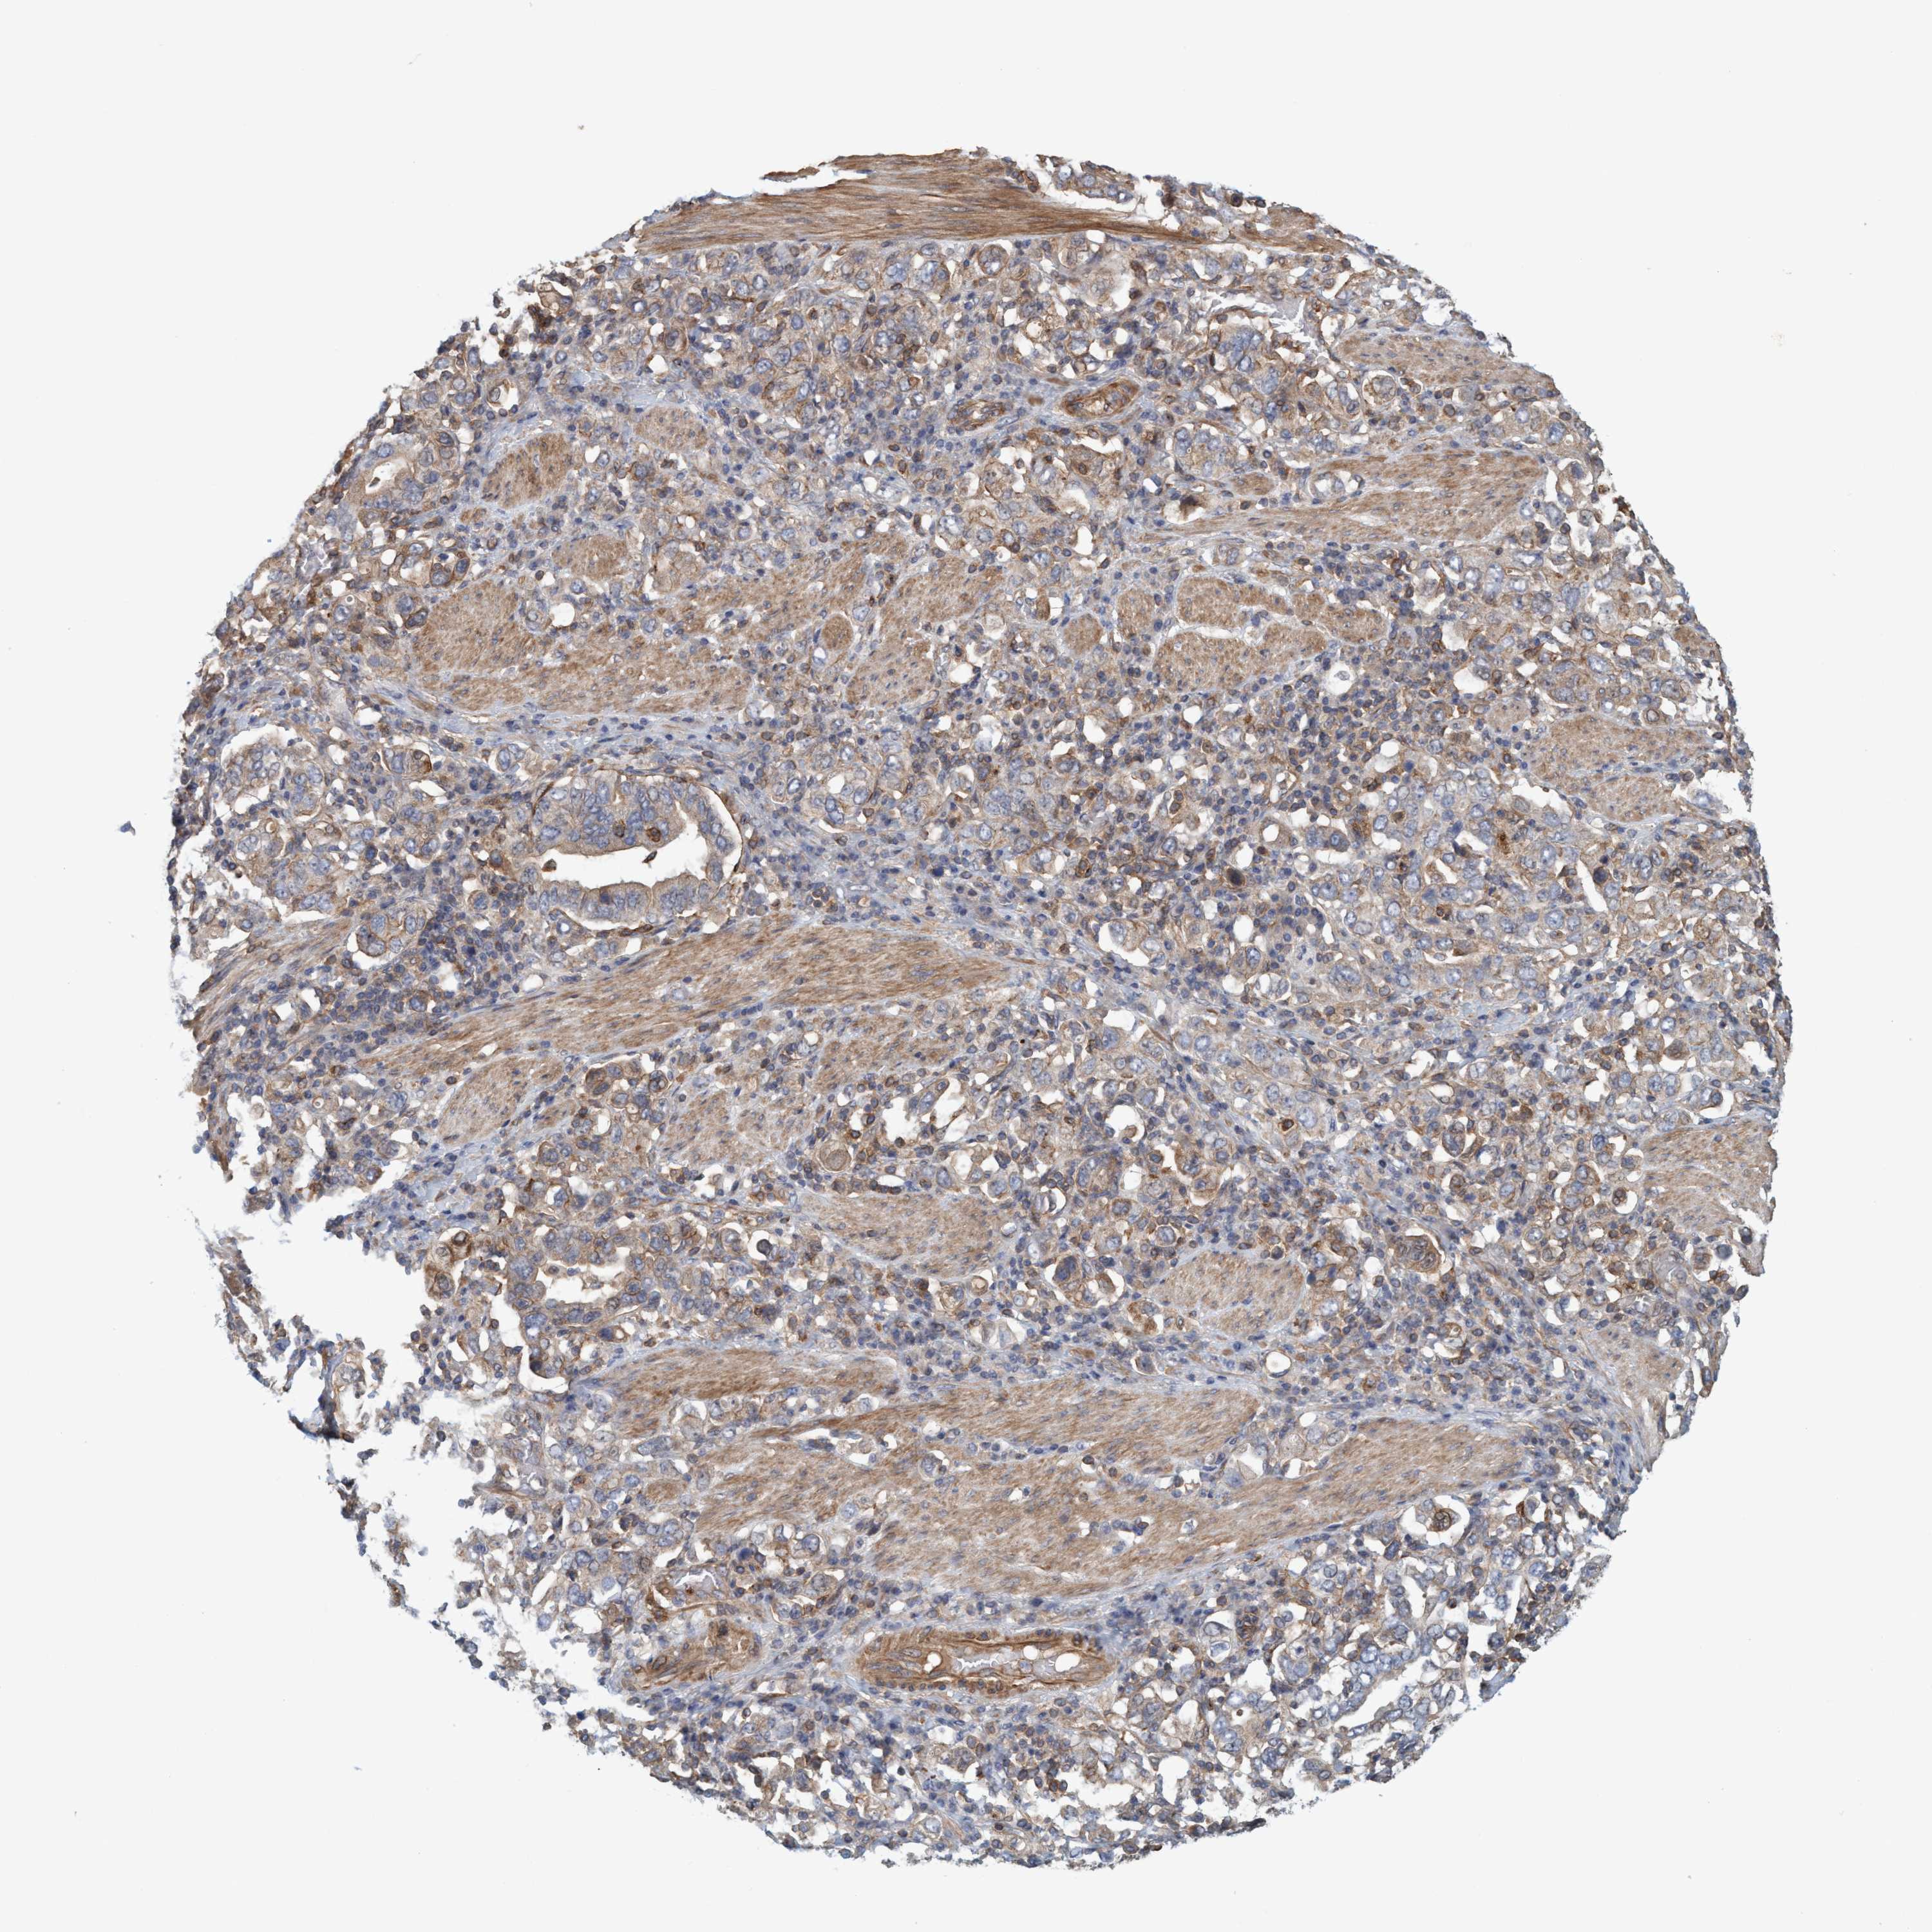

STOMACH CANCER - Protein expressioni

A mouse-over function shows sample information and annotation data. Click on an image to view it in a full screen mode. Samples can be filtered based on level of antibody staining by selecting one or several of the following categories: high, medium, low and not detected. The assay and annotation is described here.

Antibody stainingi

Antibody staining in the annotated cell types in the current human tissue is reported as not detected, low, medium, or high, based on conventional immunohistochemistry profiling in selected tissues. This score is based on the combination of the staining intensity and fraction of stained cells.

Each image is clickable and will lead to virtual microscopy that enables deeper exploration of all samples and also displays staining intensity scores, fraction scores and subcellular localization as well as patient and tissue information for each sample.

Adenocarcinoma, NOS